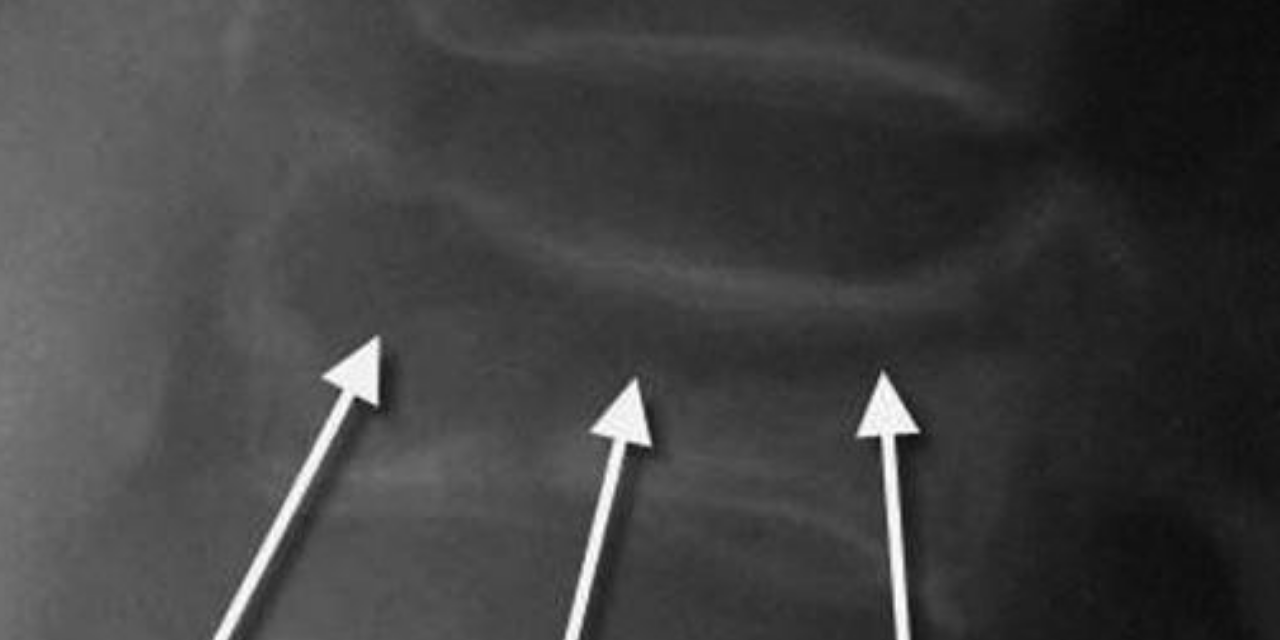

Figure 6 demonstrates multiple Kummell’s disease compression deformities on a T1 weighted image. Low signal intensity foci are seen anteriorly in these vertebral segments (indicated by the arrows).